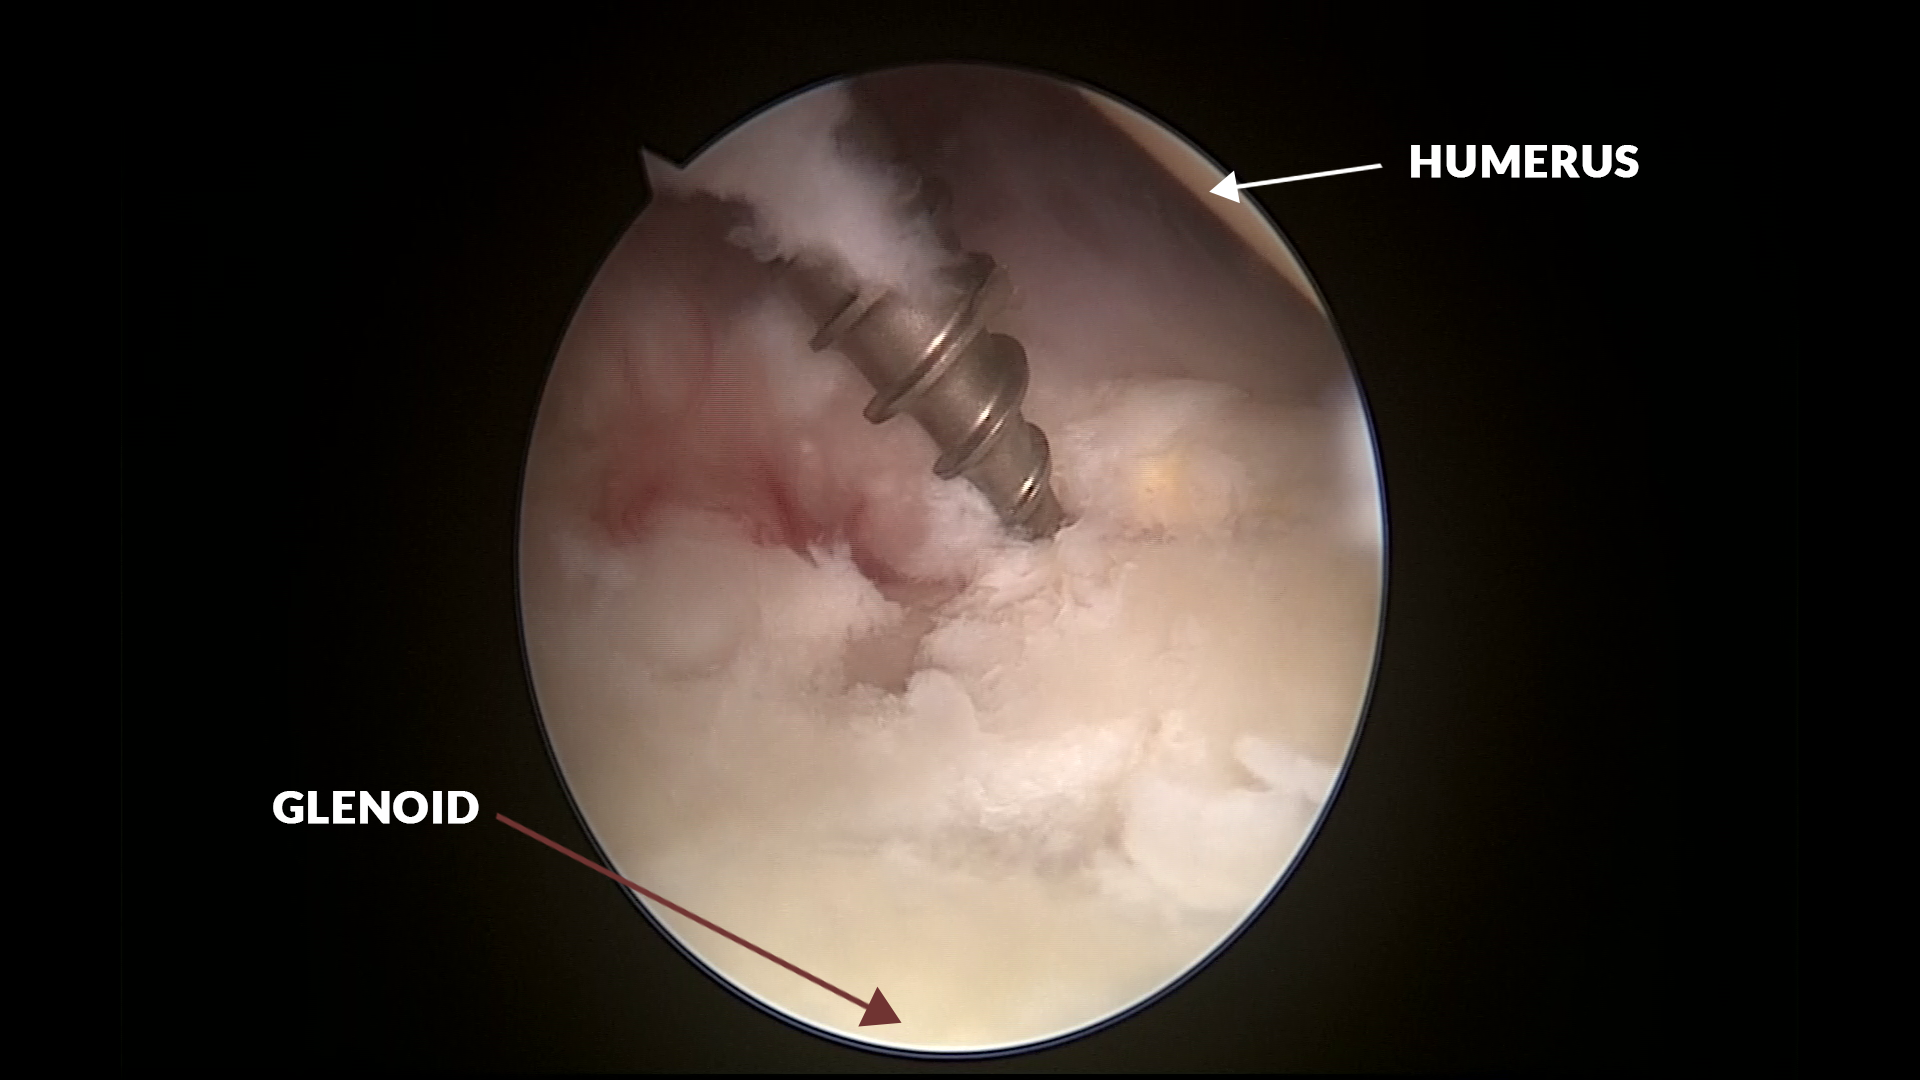

Hence the Arthroscopy revealed a SLAP with glenoid labral tear of the posterior labrum from 12 '0 clock and 5'O clock position which was partially reattached, but in a flimsy manner.

This poorly healed labrum was released with arthroscopic shaver and radiofrequency ablator and thick viscous fluid was found to come out of the Supraspinatous fossae. Manually the Supraspinatus / infraspinatus fossae were milked and the viscous fluid was thoroughly let out. The labrum and SLAP tears were repaired with suture anchors.